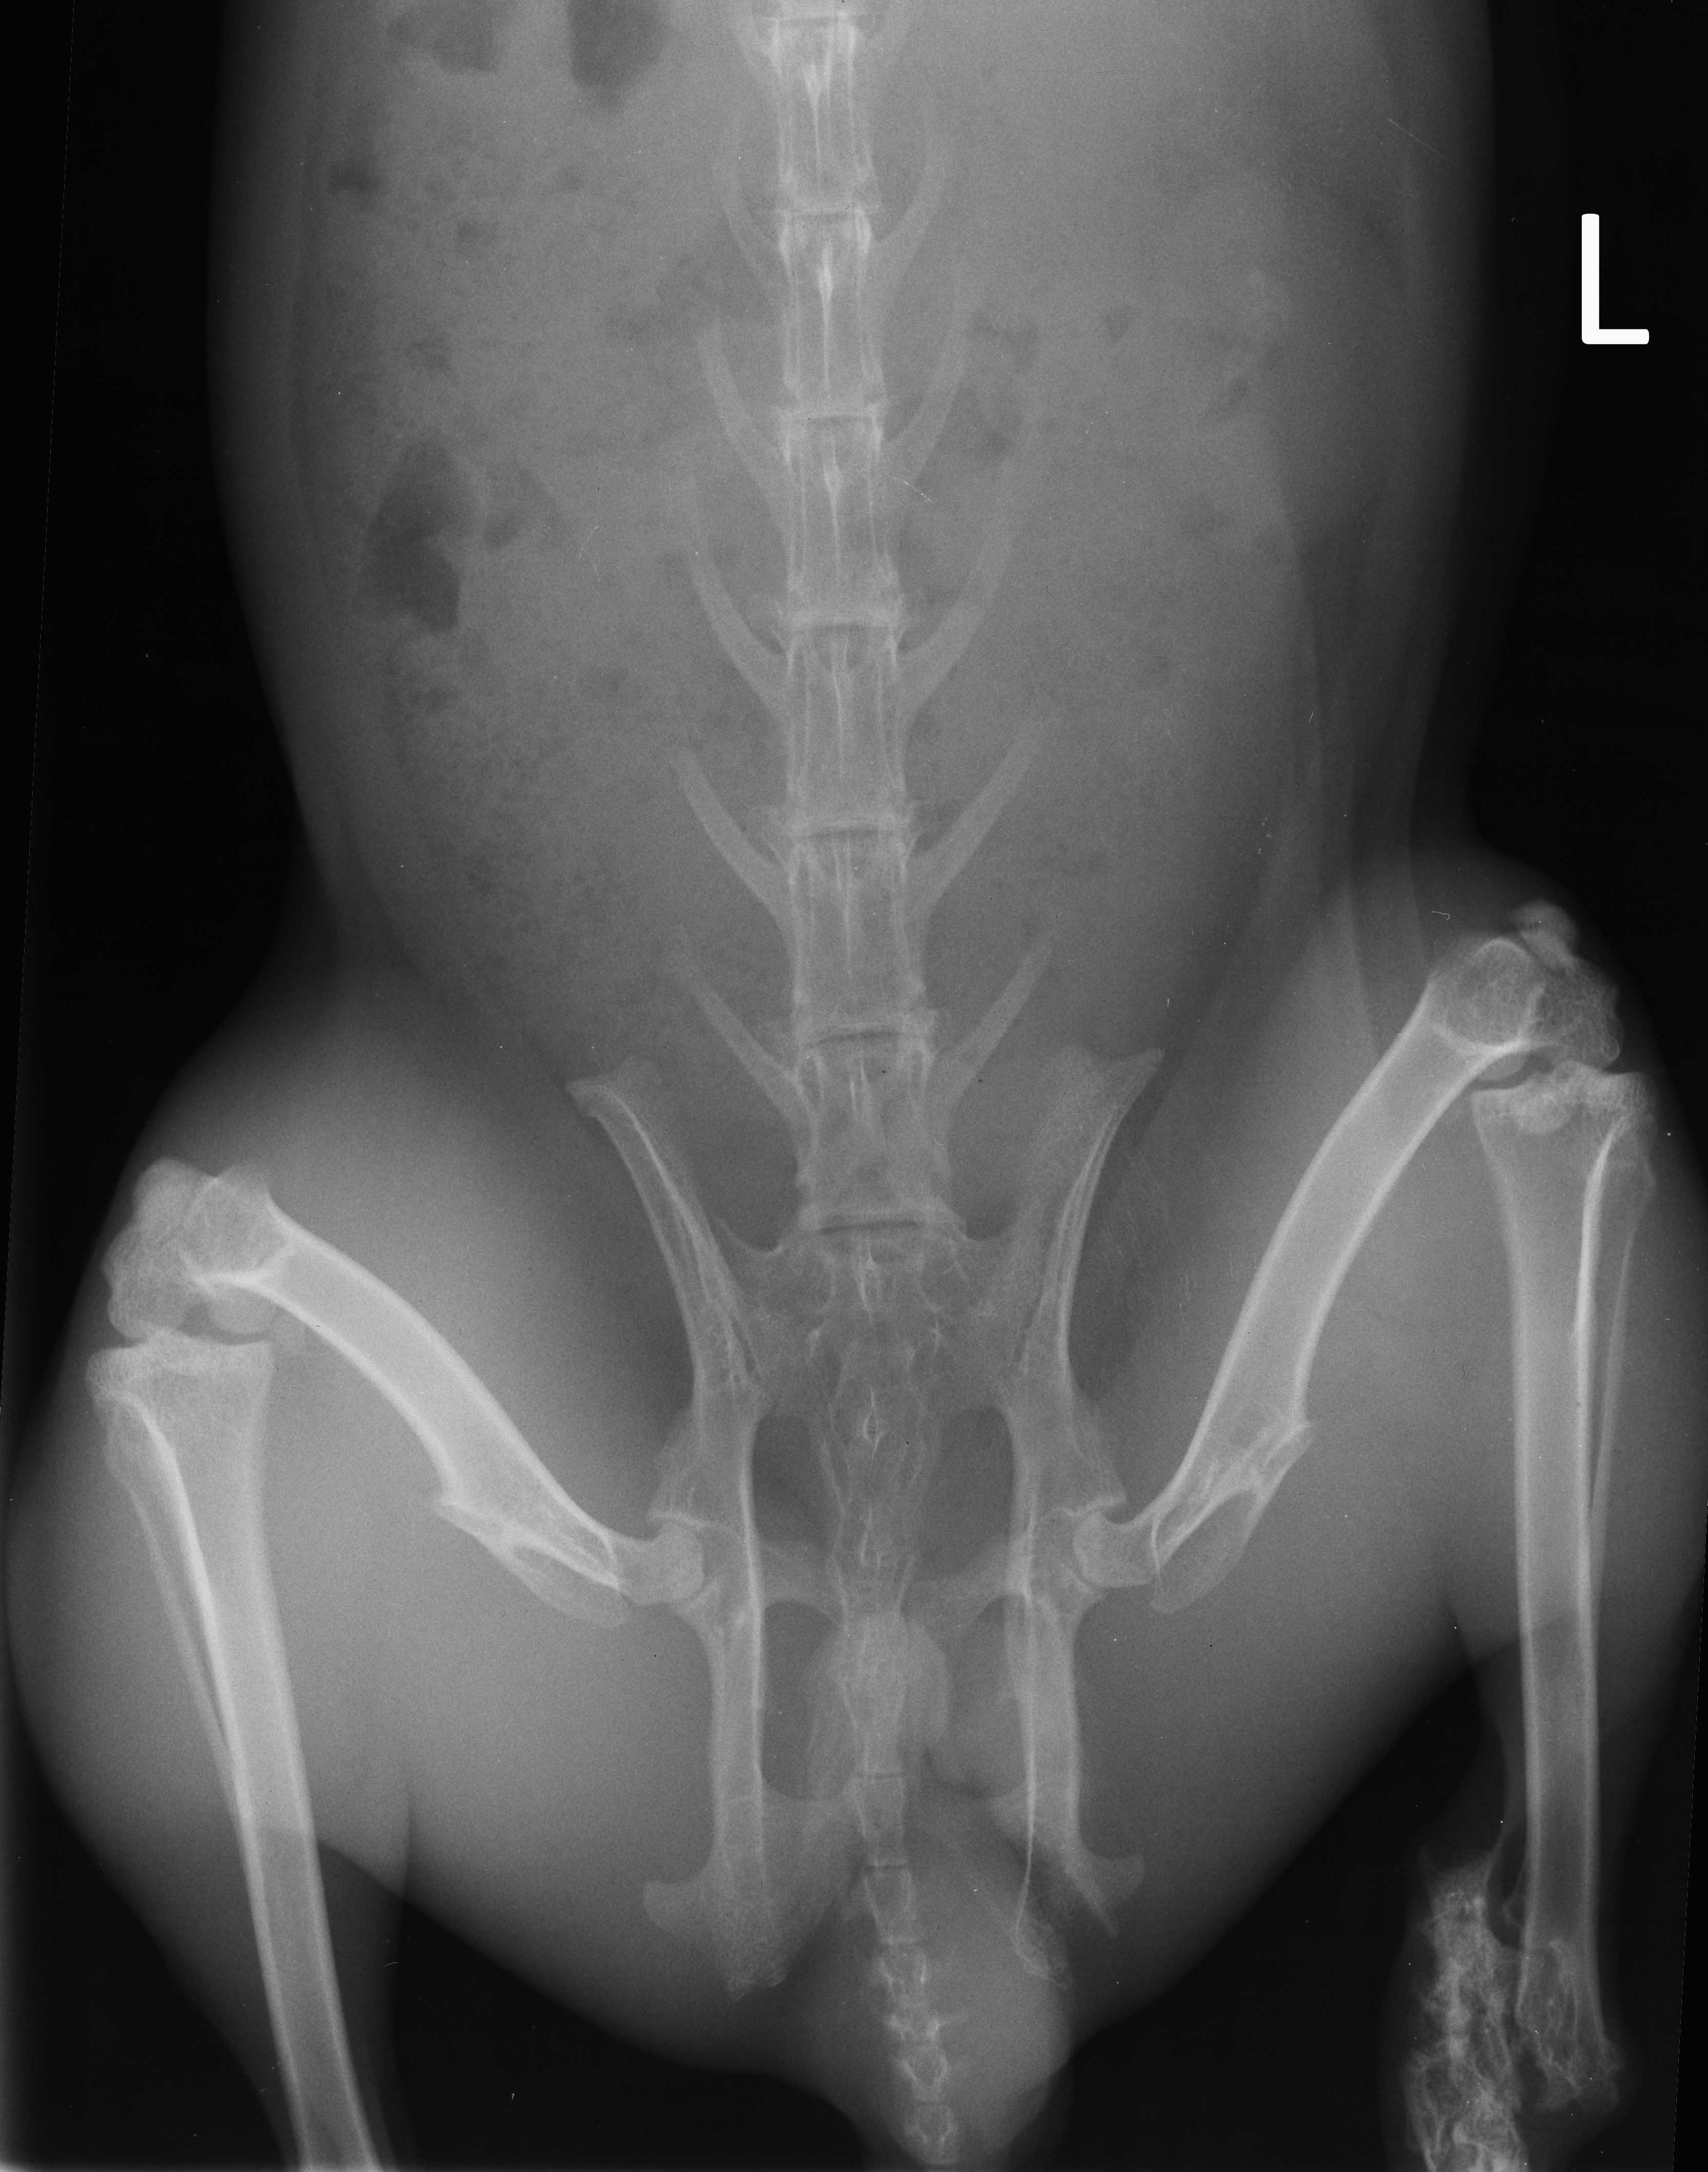

Jack's hock

Jack with fractured leg

Jacks' initial radiograph